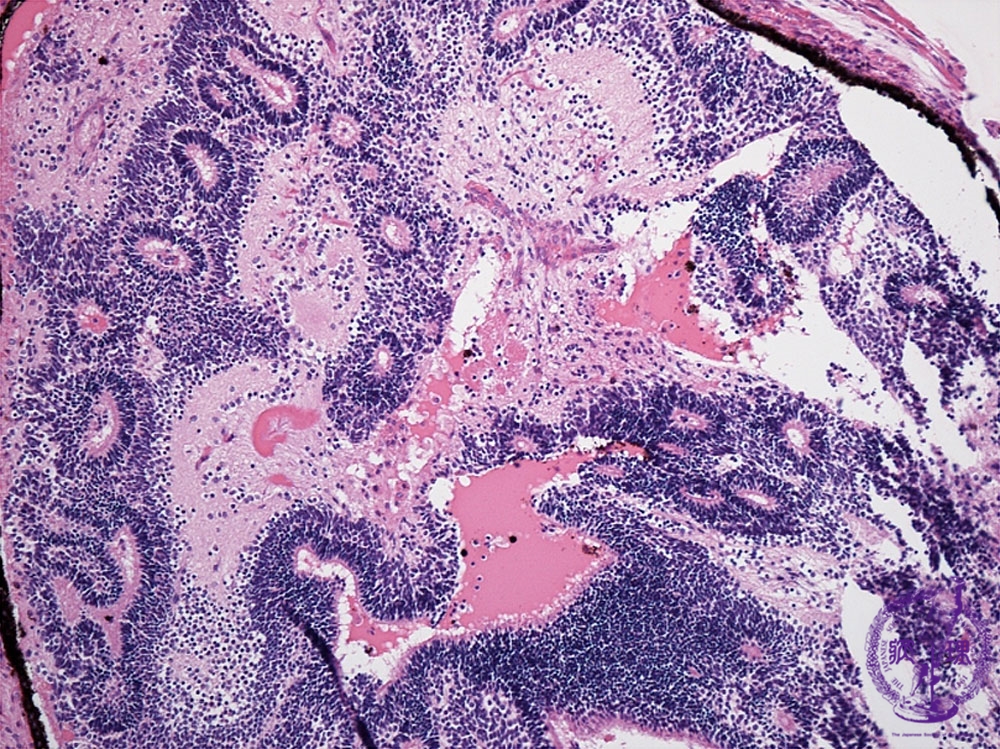

Histology (HE stain, intermediate power): Immature teratoma. Immature neuroectodermal tissue.